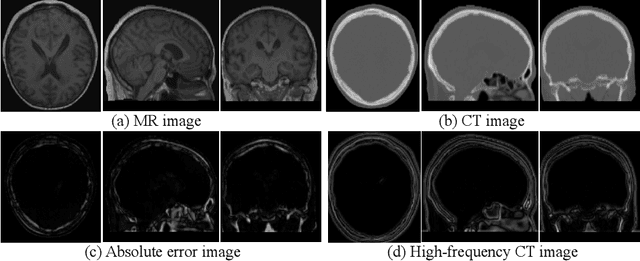

Abstract:This paper strives to generate a synthetic computed tomography (CT) image from a magnetic resonance (MR) image. The synthetic CT image is valuable for radiotherapy planning when only an MR image is available. Recent approaches have made large strides in solving this challenging synthesis problem with convolutional neural networks that learn a mapping from MR inputs to CT outputs. In this paper, we find that all existing approaches share a common limitation: reconstruction breaks down in and around the high-frequency parts of CT images. To address this common limitation, we introduce frequency-supervised deep networks to explicitly enhance high-frequency MR-to-CT image reconstruction. We propose a frequency decomposition layer that learns to decompose predicted CT outputs into low- and high-frequency components, and we introduce a refinement module to improve high-frequency reconstruction through high-frequency adversarial learning. Experimental results on a new dataset with 45 pairs of 3D MR-CT brain images show the effectiveness and potential of the proposed approach. Code is available at \url{https://github.com/shizenglin/Frequency-Supervised-MR-to-CT-Image-Synthesis}.